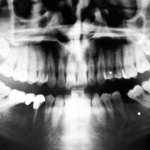

Viene proposta una metodica per diagnosticare alterazioni patologiche dell’ATM, dei mascellari, delle vertebre cervicali, mettere in relazione queste strutture anatomiche e applicare alle loro immagini i riferimenti di tracciati cefalometrici già conosciuti e/o nuove correlazioni.

La malocclusione dento-scheletrica nella patogenesi dei disordini temporomandibolari

Una relazione causale diretta fra occlusione, bruxismo e DTM non risulta scientificamente provata. Tuttavia, il concetto di malocclusione può fornire una diversa e più articolata visione e permette di prendere in ragionevole considerazione un ruolo causale indiretto dell’occlusione nei DTM, in quanto spesso coinvolta in “patologie di confine”, abitualmente considerate comorbilità autonome.